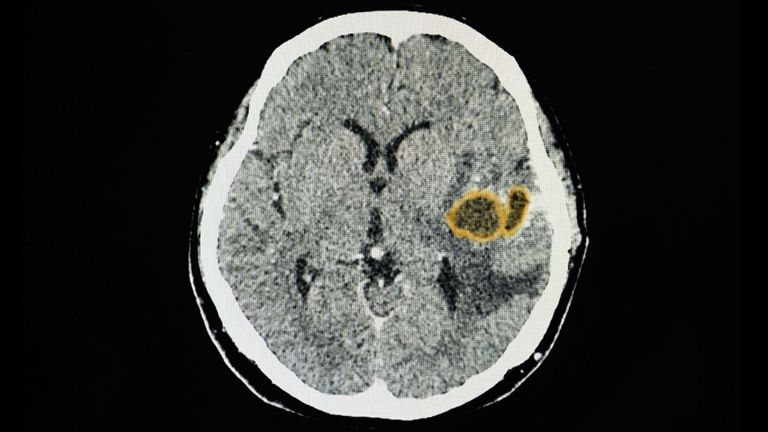

Es muy importante señalar que un absceso cerebral es una acumulación de pus e infección en el tejido cerebral, lo que puede causar convulsiones, trastornos visuales y cambios en el habla, la coordinación y el equilibrio. Su tratamiento suele incluir procedimientos quirúrgicos.